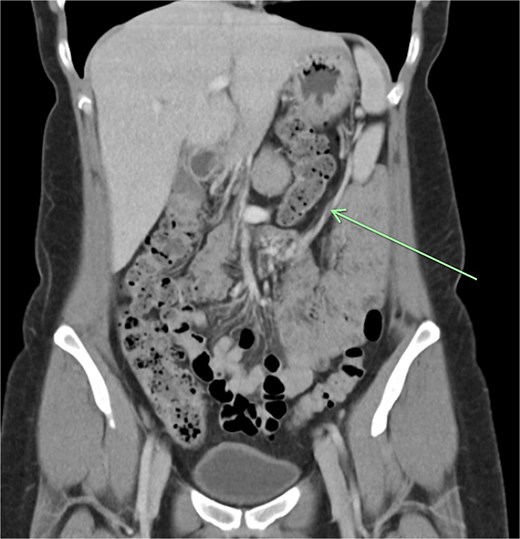

The aforementioned CT was reassessed intraoperatively together with this new information. The vascular pedicle was traced from the lesion towards the splenic vessels at the tail of the pancreas. A normal spleen was identified in the left upper quadrant (Figs 3–5). The overall impression was that this lesion represented accessory splenic tissue. The general surgery team called the patient’s next of kin, who gave consent to proceed with an excision of this wandering accessory spleen.

Long vascular pedicle leading to accessory spleen in the pelvis.

A firm solid well-circumscribed 6 cm lesion was identified in the right upper quadrant. The general surgery team was contacted for intraoperative consultation. This lesion appeared to be mobile and attached to a long vascular pedicle which was followed to the left upper quadrant, where it passed over the transverse colon towards the splenic hilum (Figs 1 and 2).

Long vascular pedicle of accessory spleen leading to left upper quadrant.